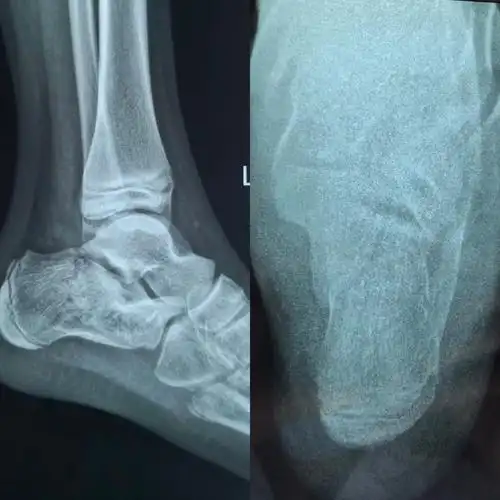

术前跟骨侧轴位片

术前跟骨轴位片与健侧对比,可见跟骨内翻角消失

术前侧轴位x线检查结果